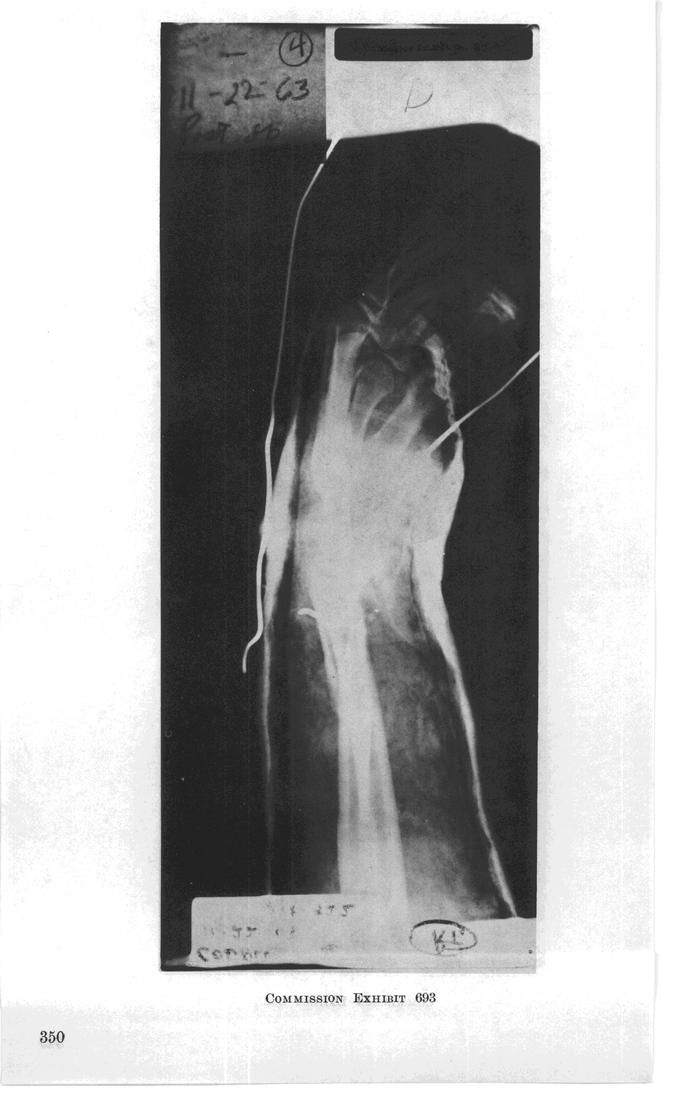

Page 350 of 928